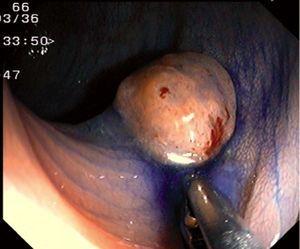

Fig. 4. Examples of protruding lesions with conventional examination and after the application of indigo carmine 0.2-0.5%. a, b) Sessile polyp. c, d) Subpedunculated polyp. e, f) Pedunculated polyp. g, h) Submucosal lesion (indigo carmine shows distinct innominate grooves, ruling out an epithelial lesion). i) Subpedunculated polyp. j) After indigo carmine application, a flat elevated lesion similar in size to the protruding segment is clarified.